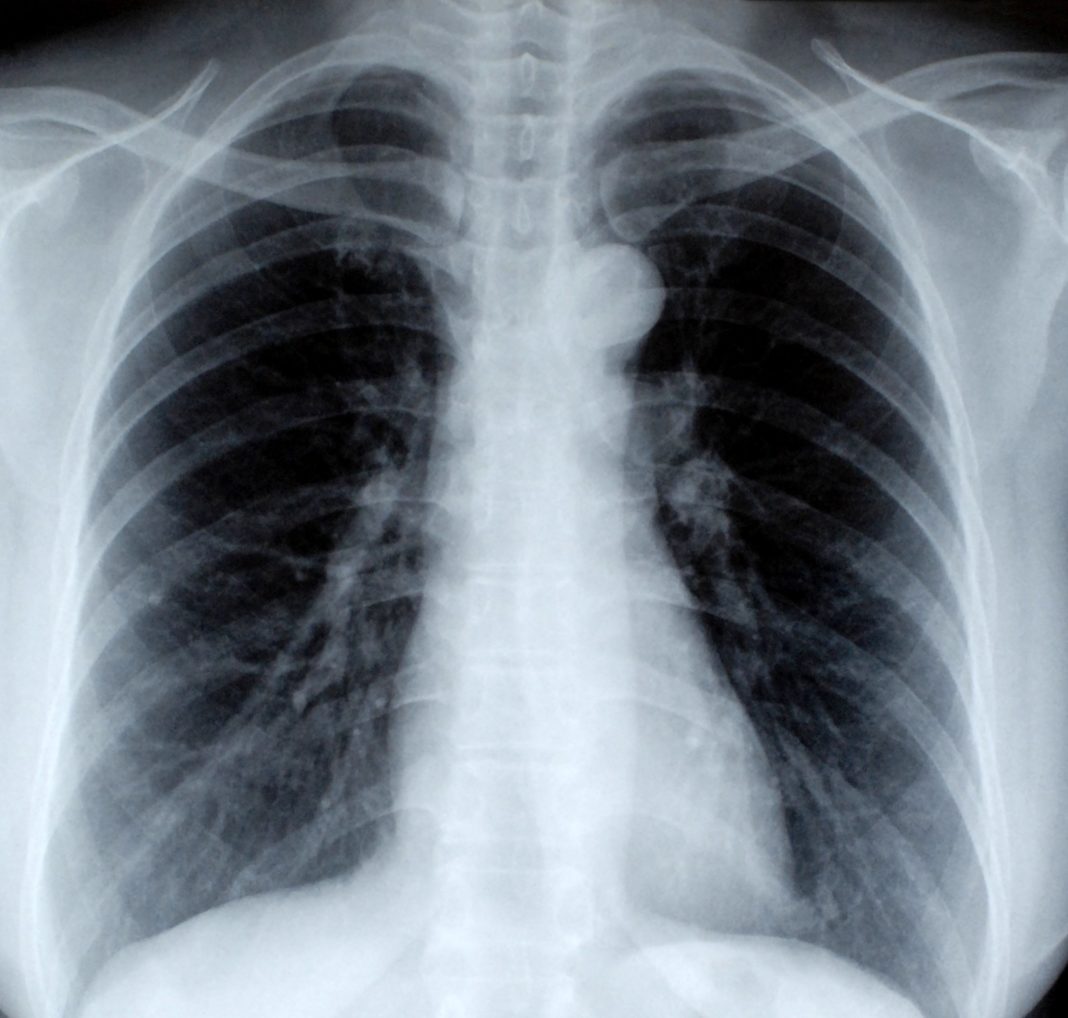

Radiografiile pulmonare sunt importante în cazul unui pacient potențial infectat cu virusul Sars-Cov-2. Acesta poate provoca pneumonie, iar prin examinarea radiologică medicii pot detecta semnele infecției și măsura în care virusul a afectat plămânii pacientului.